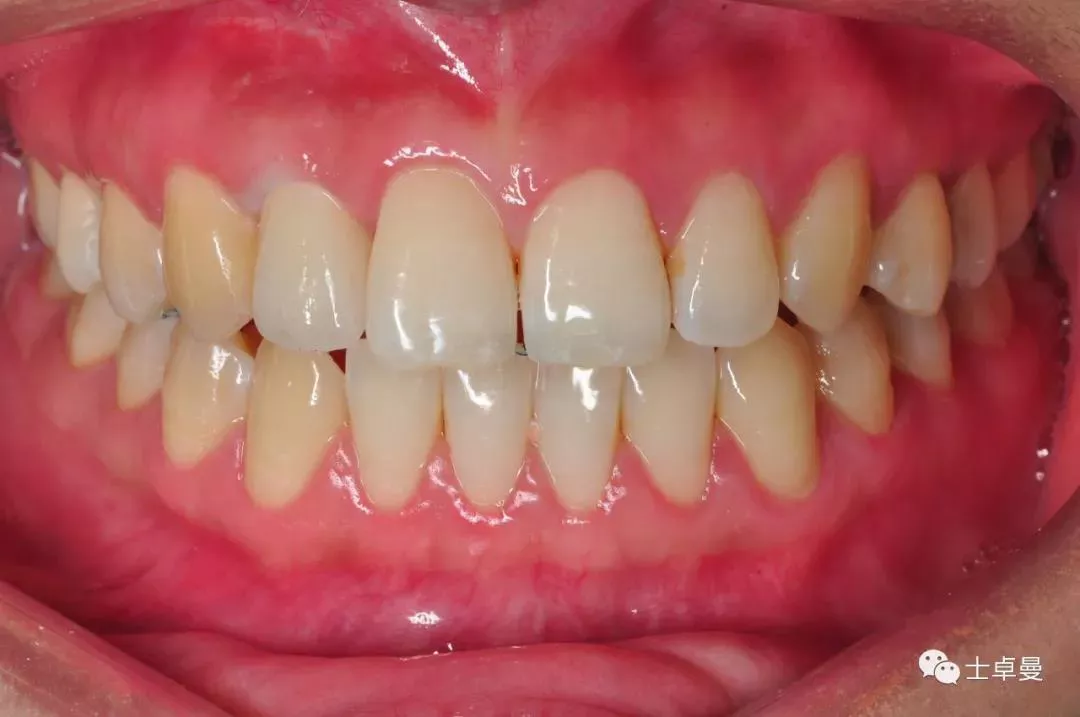

·        唇侧龈缘曲线完好,与邻牙协调,牙龈质地健康,无炎症,薄龈型;

龈缘曲线高度协调一致

口内完成修复当日

完成修复一年后复查